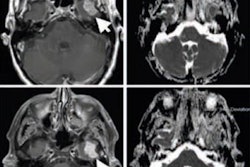

MRI is known to detect a wide range of abnormalities in tissue surrounding soft-tissue sarcomas, which could develop into high-grade tumors beyond the primary cancer site. The presence of infiltrative growth pattern and increased edemas have been associated with high-grade soft-tissue sarcoma, which naturally can lead to adverse consequences for patients.

The researchers' goal was to evaluate the area around the sarcoma using MRI to record pretreatment conditions, the efficacy of neoadjuvant chemotherapy, and correlate patient response with their outcomes to determine how these factors might predict survival.